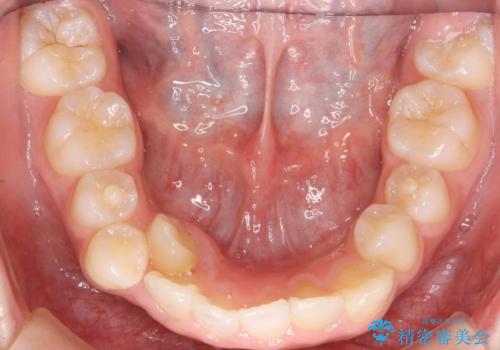

- 前歯のガタガタを主訴に来院。

上の前歯は、小さいころにぶつけて折ったとのことで、神経が死んでおり、根の治療が必要な状態でした。

神経の治療を先に行い、ワイヤー矯正を行いました。

上下の小臼歯を抜歯しています。

左上の前歯は神経が死んでおり治療が必要な状態でした。また、右上の前歯も根の先に感染がありましたので治療を行いました。

また、プラスチックでつぎはぎになっていたため、虫歯を取りしっかりとしたクラウン(被せもの)としました。

前歯の変色及び、ガタガタもしっかりなおり、満足していただきました。